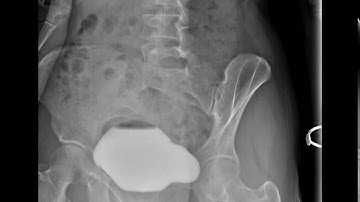

Voiding Cystourethrogram (VCUG)